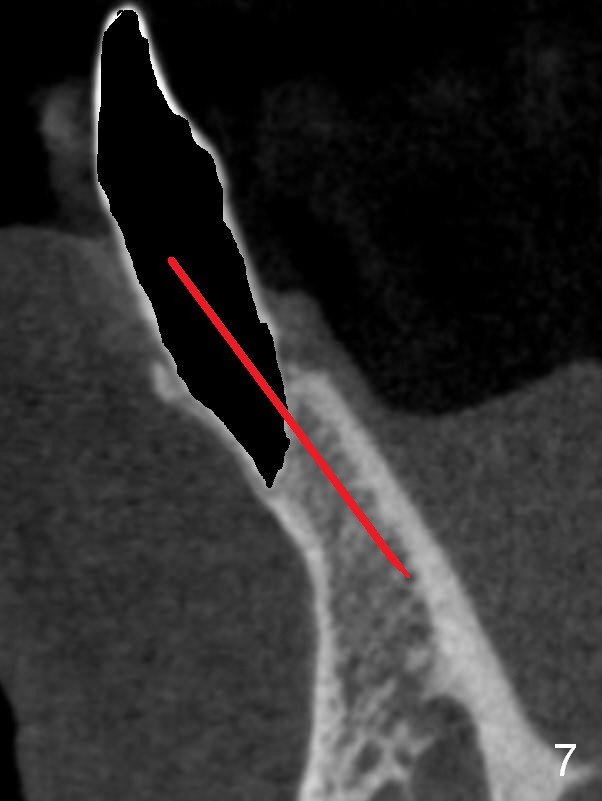

A 74-year-old man has several missing teeth (Fig.1).  His 1st goal is to replace the lower left lateral incisor (Fig.2).  The residual root has an apical lesion (Fig.3 *).  To describe intraop findings, a CT image of a different patient is used (Fig.4 coronal section; B: buccal; L: lingual).  After extraction, the buccal plate is found to be thin and low (Fig.5 arrowheads).  A 1.5 mm pilot drill (Fig.6 red line) is used to initiate osteotomy in the lingual plate of the socket.  Once the drill penetrates the lingual plate, the trajectory changes and the depth is 17 mm from the gingival margin (Fig.7).  A PA is taken (Fig.8); it appears that the osteotomy can be extended more apically.  When the pilot drill extends to 20 mm, there is sudden empty feeling.  The lingual plate has perforated (Fig.9).  A new osteotomy is established buccally (Fig.10 pink).  To avoid buccal plate perforation, especially in the buccal undercut area (>), the coronal end of the drill has to be tilted buccally (<--).  An angled abutment (3x20 mm, 15°) is placed (Fig.11,12).  The abutment is modified (Fig.13,14) to accommodate an immediate provisional (Fig.15,16 P).  Perio dressing is to be applied to prevent the bone graft from getting dislodged buccally (Fig.15).  The dressing is in place 7 days postop (Fig.17).